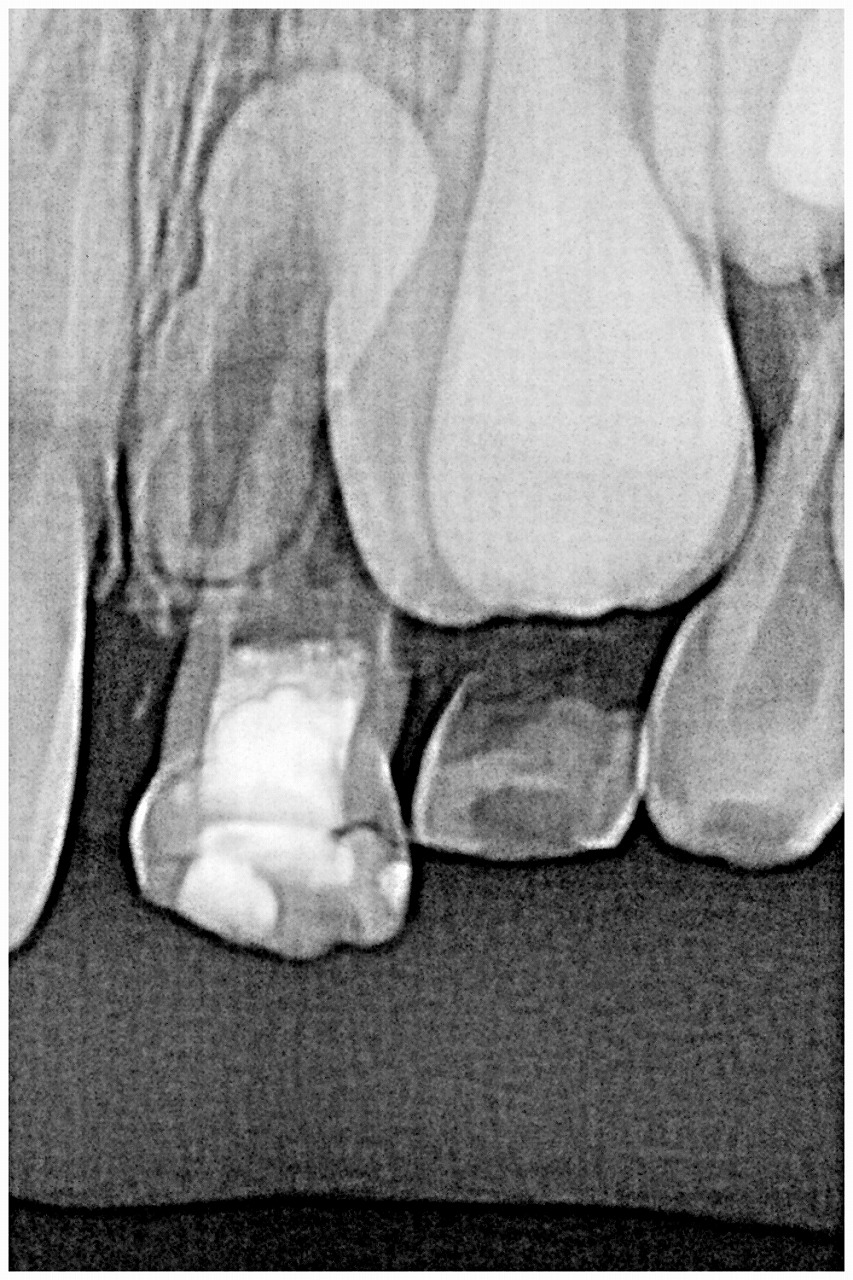

過剰歯の仕業かと考えデンタルレントゲンを撮影しています

抜歯に際してCTにて把握します